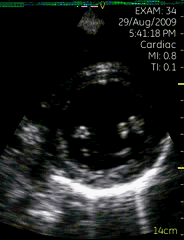

心尖四腔切面

| 图像名称: | 心尖四腔切面(二维) |

| 心尖四腔切面(彩色) | | 介绍重点: | 心脏各腔室大小正常、瓣膜运动协调; |

| 左房增大,二尖瓣启闭受限; |

| 左房增大,二尖瓣舒张期前向血流速度增快,收缩期可见蓝色反向血流; | | 临床用途: | 评估心脏各腔室大小,瓣膜结构与功能;(正常图像) |

| 风湿性心脏病:二尖瓣狭窄伴关闭不全; |